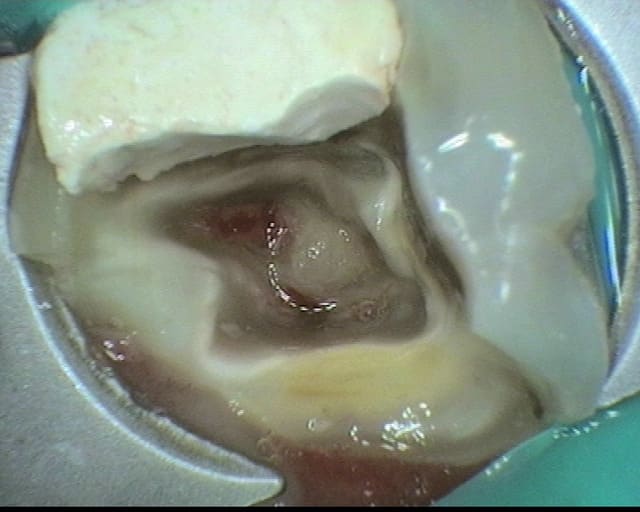

Je profite d'une pause pendant les vacs pour mettre en ligne l'ultime endo avant les vacances estivales (37).

Première effraction du plancher depuis mon diplôme en 2005.

L’éviction des pulpolithes a été réalisée par ultrason. J'ai suivi une coloration entre ce que je pensais être de la dentine réactionnelle et le reste de chambre pulpaire comblée par un gros pulpolithe.

J'ai placé un MTA, CVI par dessus. Je reprends l'endo en septembre.

A votre avis, quels éléments m'ont induit en erreur ? Sur ce type de cas, avez-vous une approche différente ?